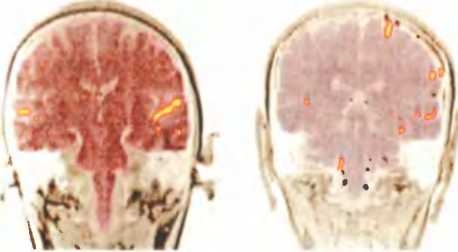

Когда испытуемый обращает внимание на другую половину поля зрения, мозговая активность перемещается из одного полушария в другое. Слева показан мозг человека, смотрящего на объект слева от себя (активируется правое полушарие), справа — мозг человека, смотрящего на объект справа от себя (активируется левое полушарие).